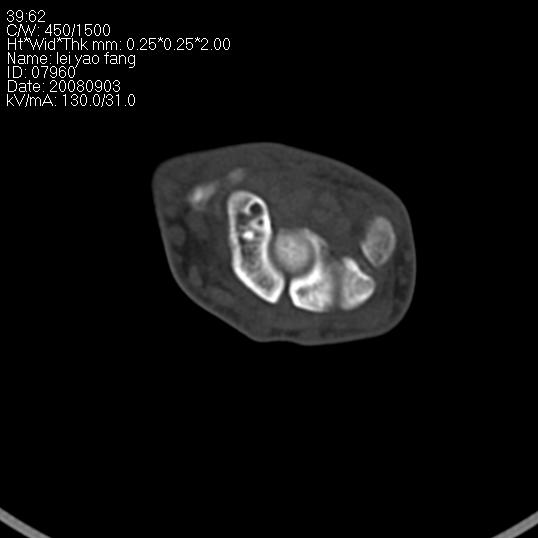

以下是引用杀毒软件在2008-9-4 17:41:00的发言:[br]考虑----舟骨囊肿